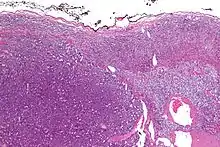

| Micrograph of an adrenocortical carcinoma (left of image – dark blue) and the adrenal cortex it arose from (right-top of image – pink/light blue). Benign adrenal medulla is present (right-middle of image – gray/blue). H&E stain. | |

Adrenal tumors are often not biopsied prior to surgery, so diagnosis is confirmed on examination of the surgical specimen by a pathologist. Grossly, ACCs are often large, with a tan-yellow cut surface, and areas of hemorrhage and necrosis. On microscopic examination, the tumor usually displays sheets of atypical cells with some resemblance to the cells of the normal adrenal cortex. The presence of invasion and mitotic activity help differentiate small cancers from adrenocortical adenomas.[9] Several relatively rare variants of ACC include: